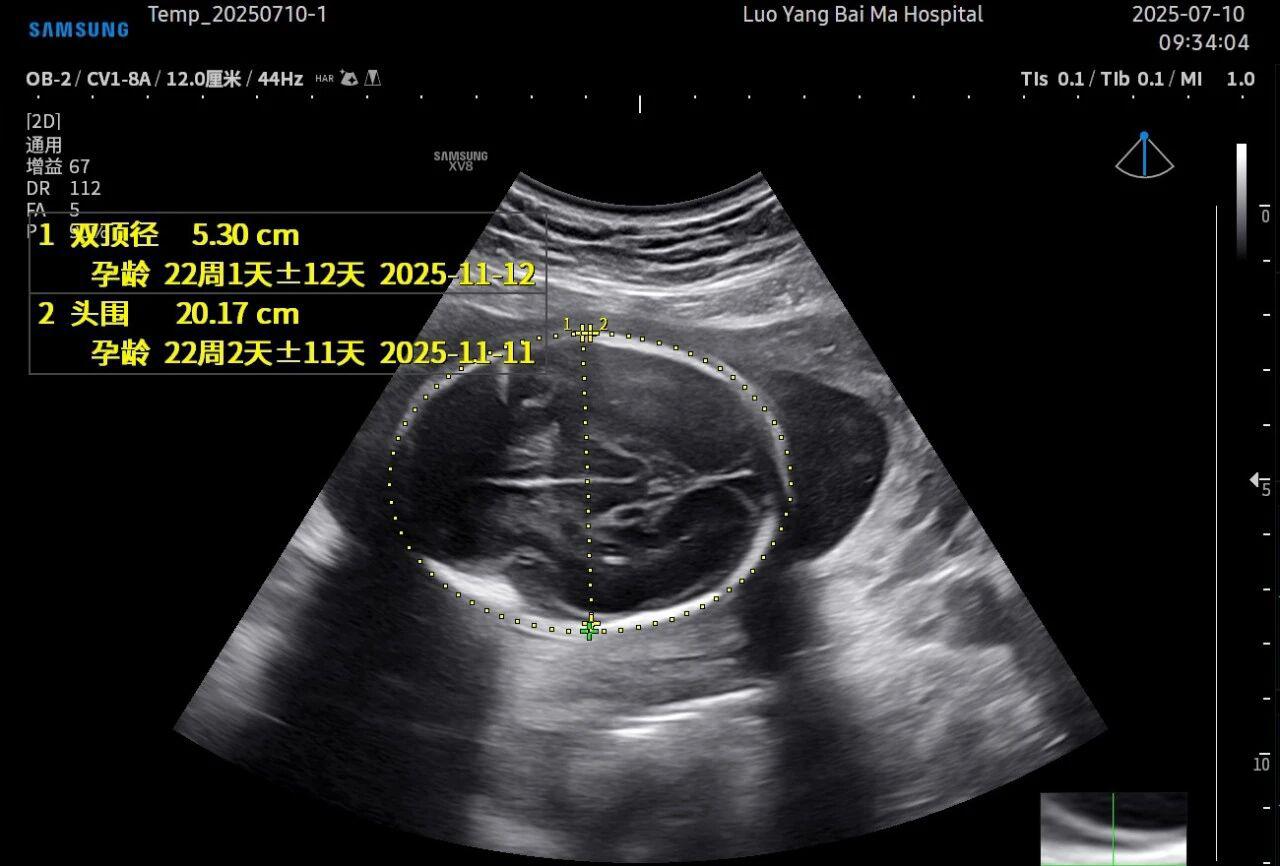

3. AI智能辅助,提升诊断效率与客观性

这是5D技术的核心优势之一。系统内置了强大的智能化大数据分析功能和AI辅助诊断工具。例如,在进行胎儿颈项透明层(NT)测量、胎儿长骨(LB)测量等关键生物学指标评估时,5D智能系统可以自动识别解剖层面、智能勾勒测量范围并进行计算。这不仅大大缩短了检查时间,更重要的是,它通过标准化的智能算法减少了因人为操作可能产生的误差,使诊断结果更加客观、可靠。

• 5D彩超检查通常建议在孕20-26周,尤其推荐在孕22-24周进行。此时胎儿大小适中,羊水量充足,图像清晰度较高。